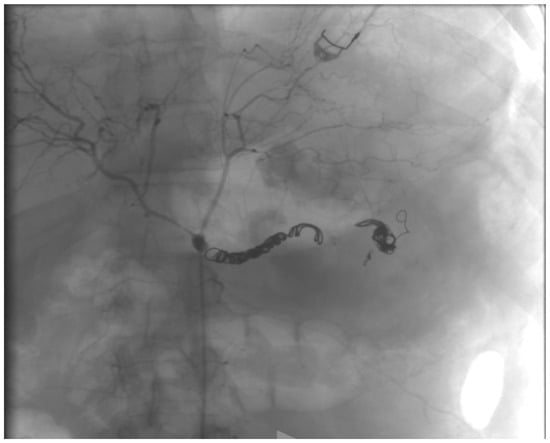

2.1. Case Report